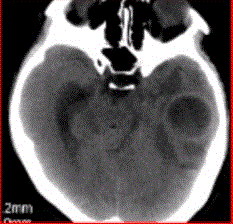

问题 患者女,26岁,头痛、低热10d余,既往有左侧慢性中耳炎病史。CT表现如下图。 初步诊断为

选项 A.脑脓肿 B.胶质瘤 C.脑血肿 D.脑梗死 E.脑囊虫

答案 A